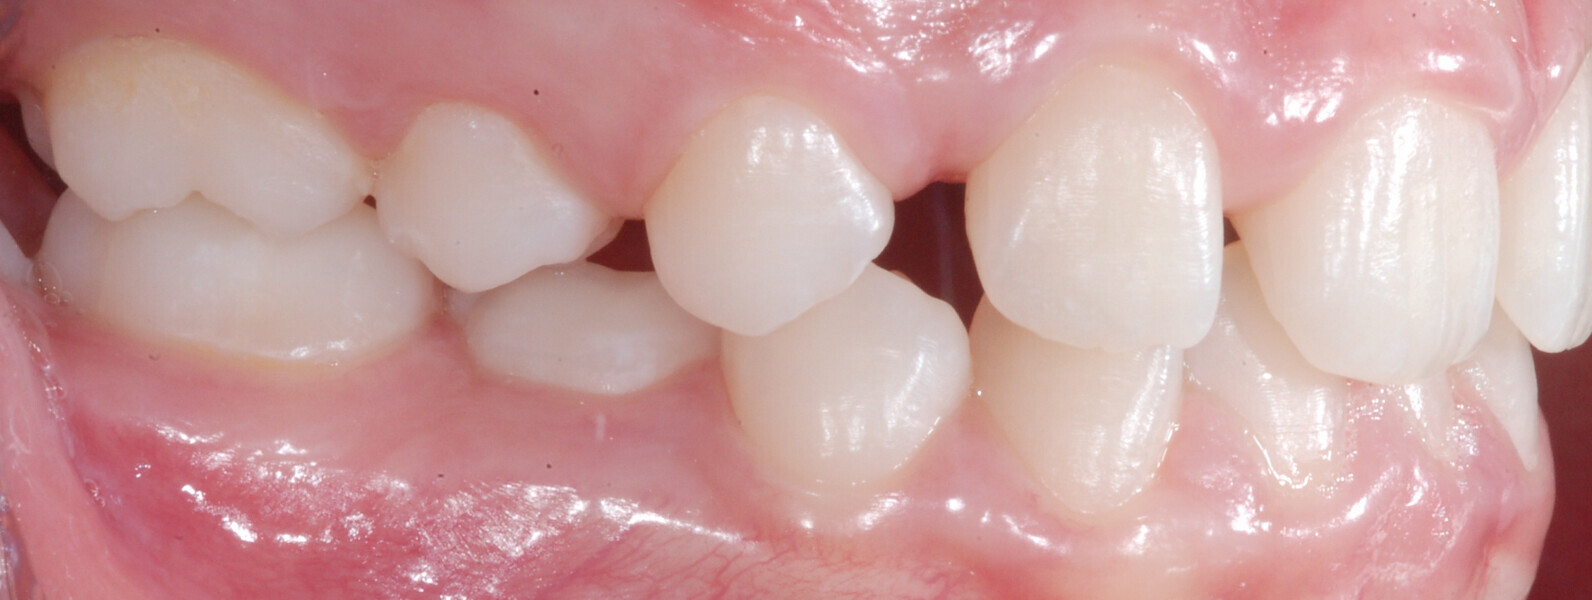

A 14-year-old female patient presented with the chief complaint of midline deviation and dental crowding in both arches. Facial analysis showed a hypodivergent growth pattern, a normal nasolabial angle, a harmonious profile and proper chin projection. Clinical examination revealed a Class III skeletal relationship (ANB = 0°) and Class I molar relationship. The maxillary right canine was absent, and this had led to space loss and mesial drift of posterior teeth on the right side, resulting in a slight Class II molar relationship. The maxillary left canine had erupted in a high position. The mandibular arch displayed crowding despite the agenesis of the right second premolar and the persistence of the primary molar (Figs. 3–11). The radiograph showed the probably premature loss of the maxillary right primary canine and consequently impacted maxillary right permanent canine, and the agenesis of the mandibular right second premolar and the mandibular right third molar (Fig. 12).

Fig. 3

Fig. 4

Fig. 5

Fig. 6